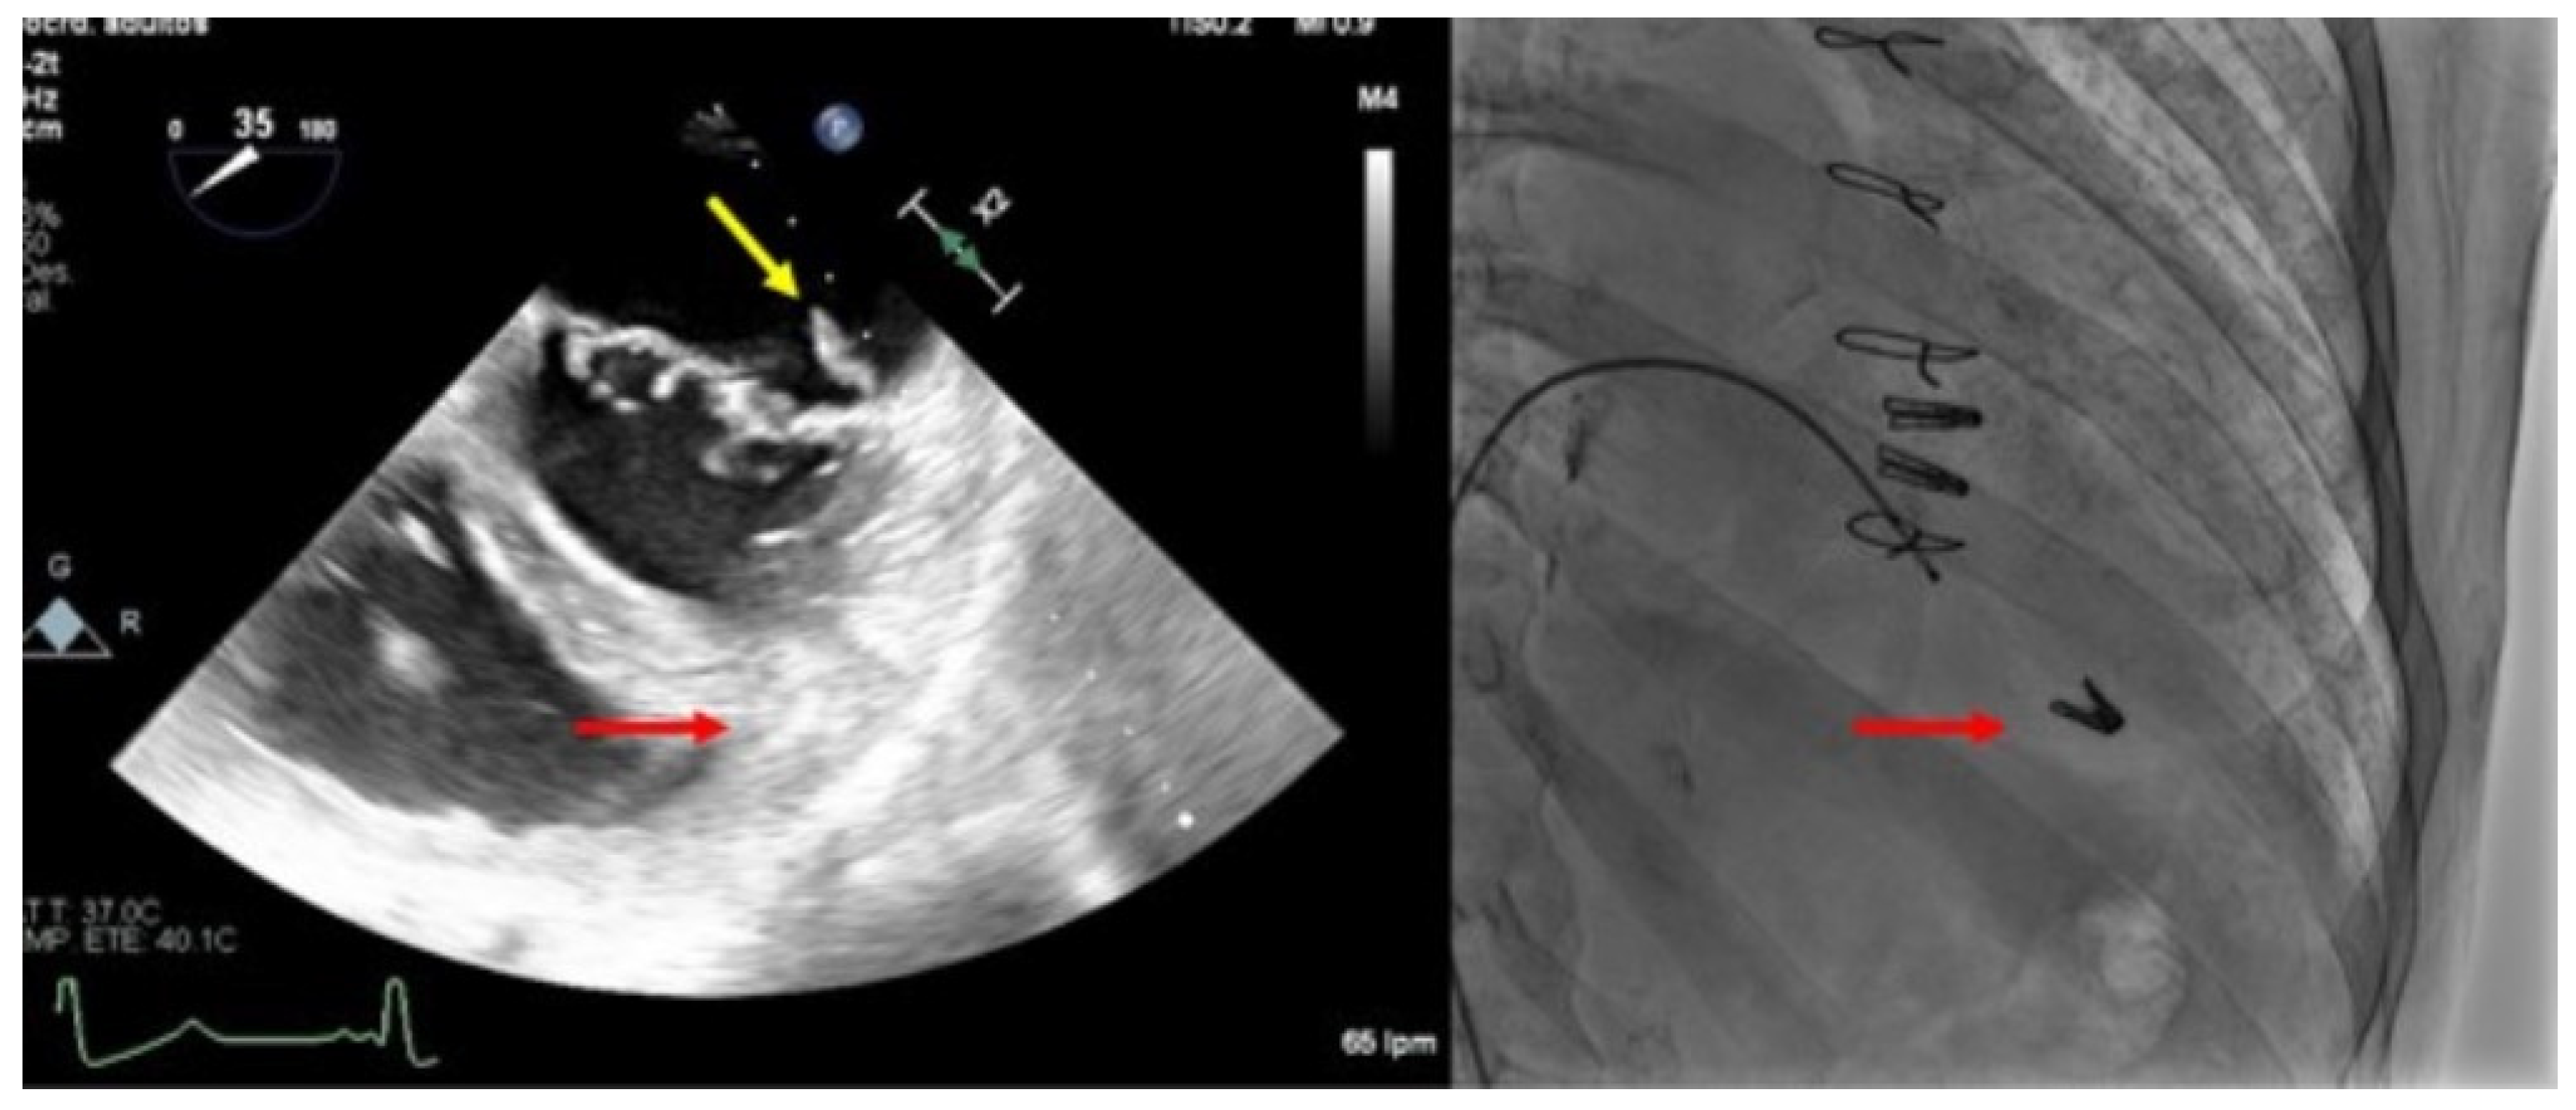

Figure 6.

Clip embolization. (Left) Two-dimensional transesophageal echocardiogram showing a posterior leaflet prolapse (yellow arrow) after retrograde embolization of a clip to the right ventricle through the procedural atrial septal defect (red arrow). (Right) Fluoroscopy image at the end of the procedure showing two clips implanted in the mitral valve and another one embolized in the apex of the right ventricle (red arrow).